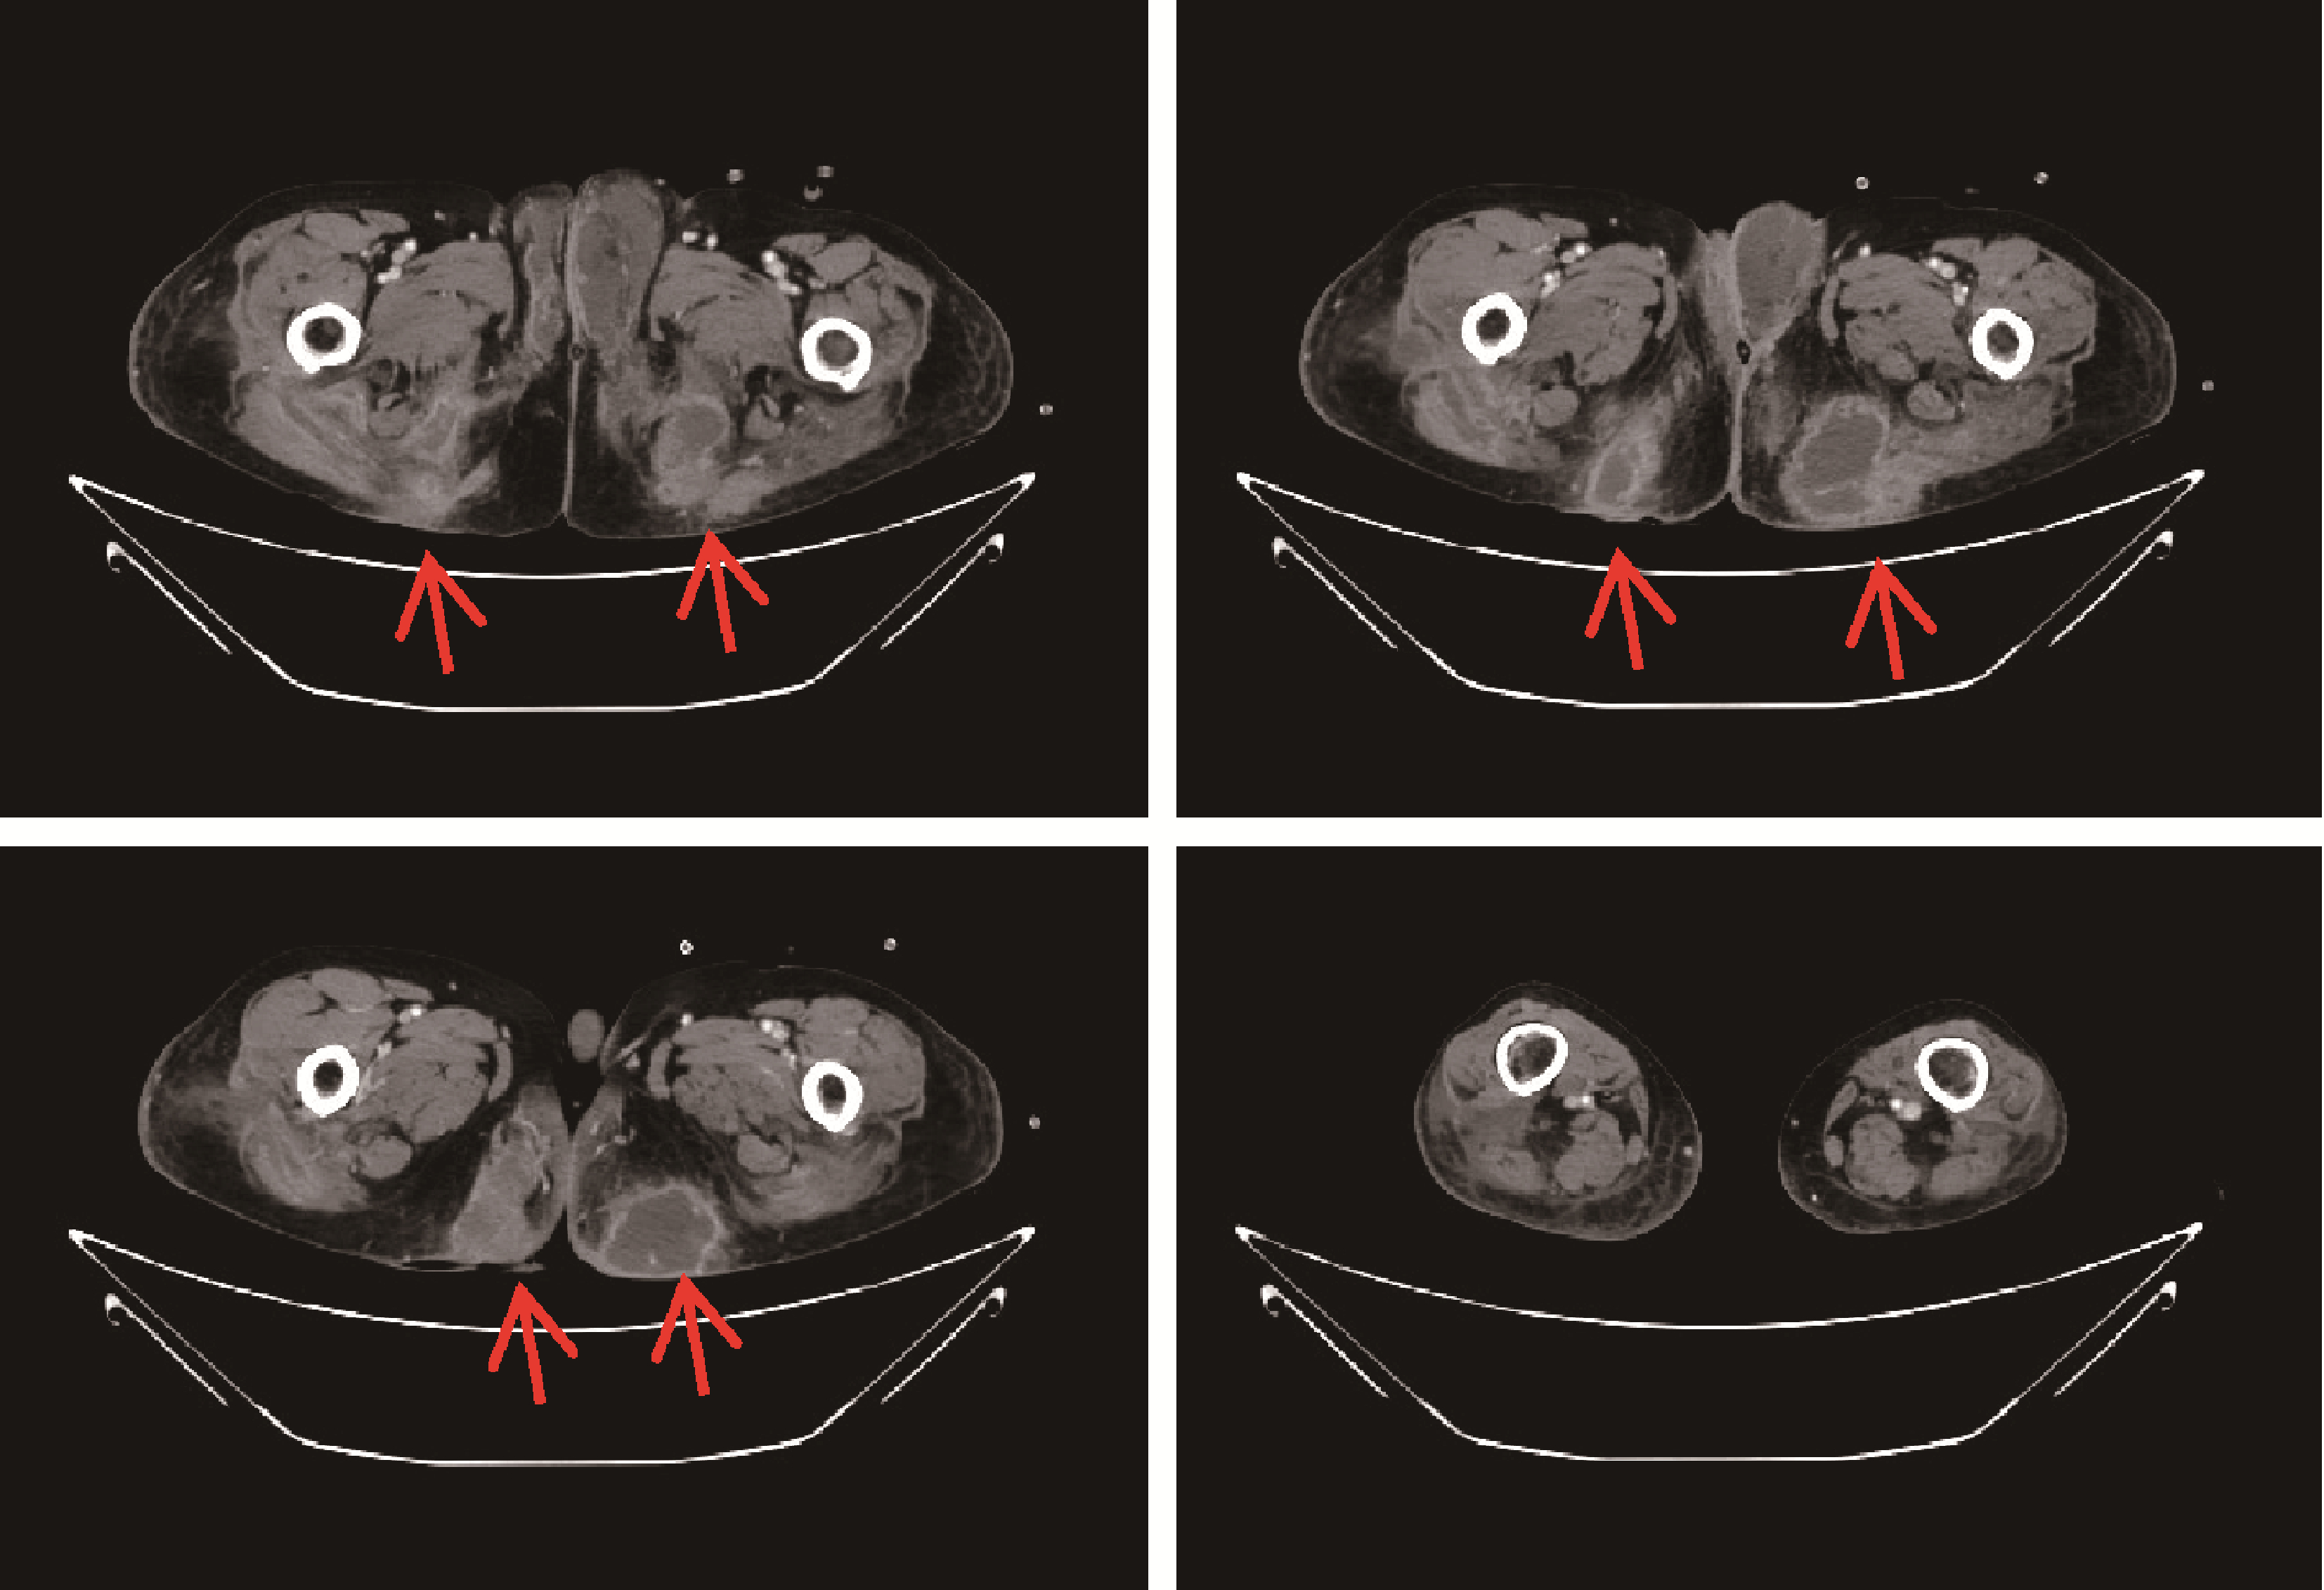

SchulzeM, OverkampD, JoanoviciuS, 等. 坏死性筋膜炎的CT表现[J]. 放射学实践, 2008, 23 (11): 1290- 1291.